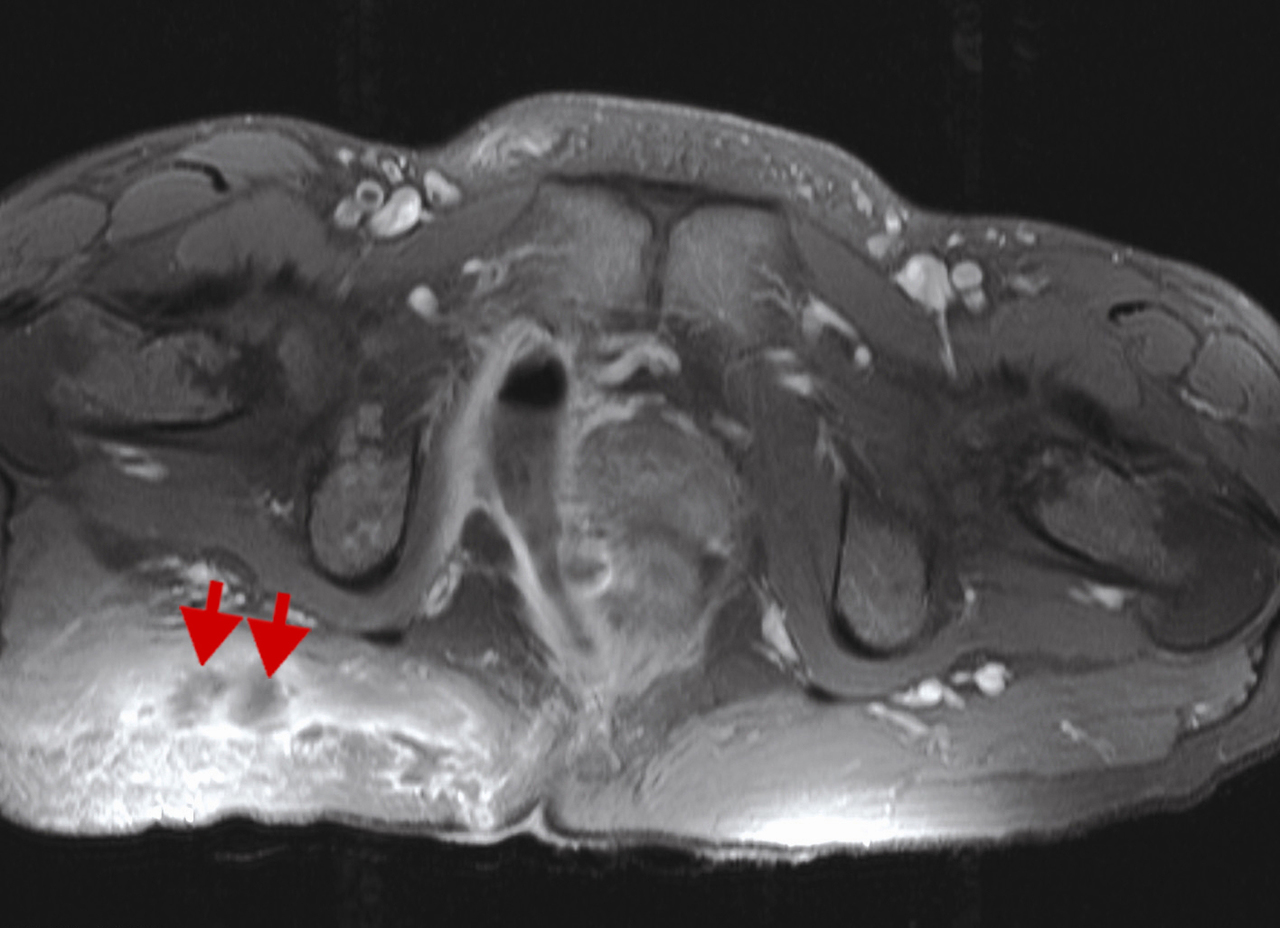

Atteine périnéale sévère avec abcès de la fosse iliaque droite (étoile jaune) et trajets fistuleux multiples (flèches rouges) au niveau fessier. IRM en séquence T1 avec injection de gadolinium et saturation de graisses.